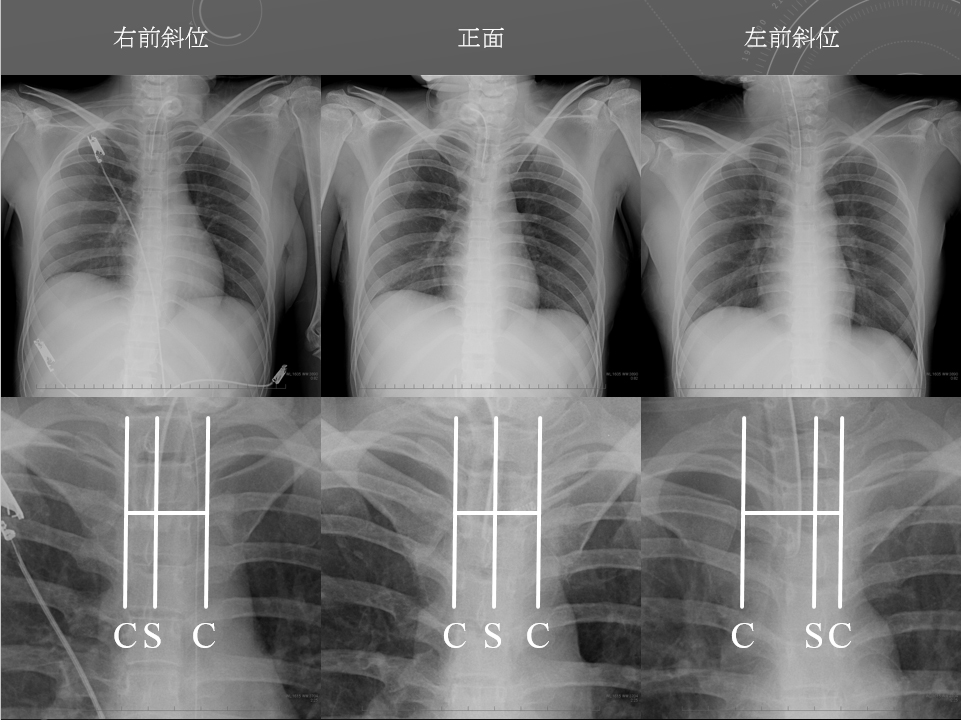

左前斜位

右前斜位